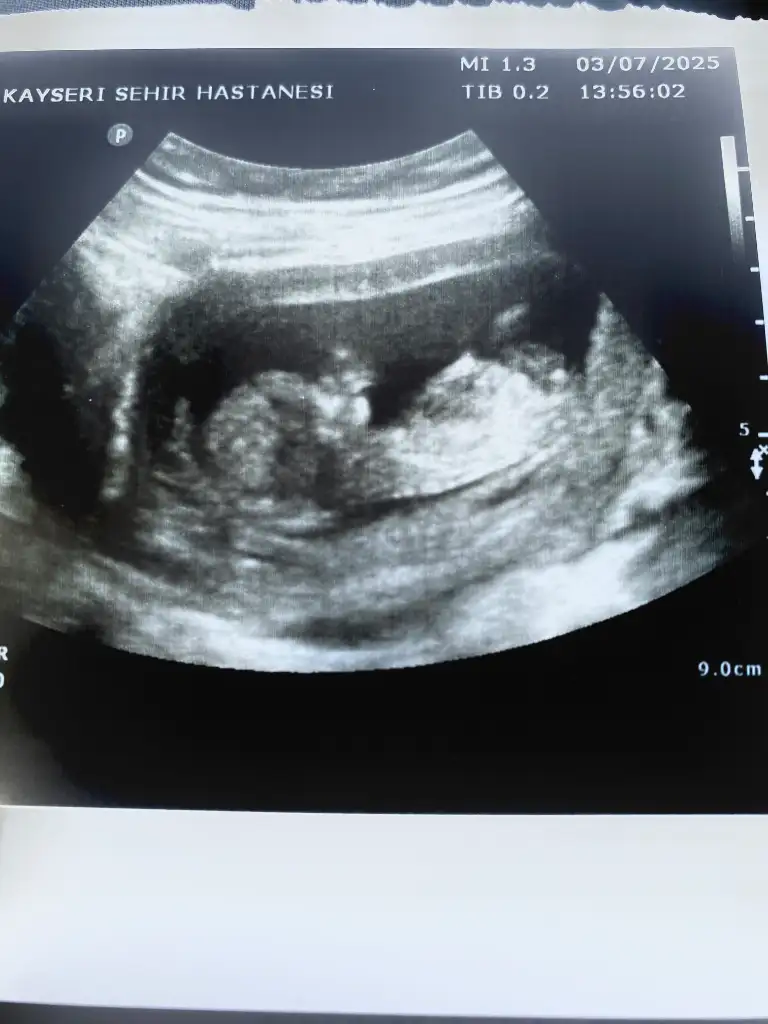

Kızlar 14 haftalık yeni ultrason doktor yine bilgi vermedi cinsiyet için varmı tahmini olan

bunlarda benim torunlarım 13 haftalık ,

doktor erkek demiş , ama yanılma olurmu anlayan var mı